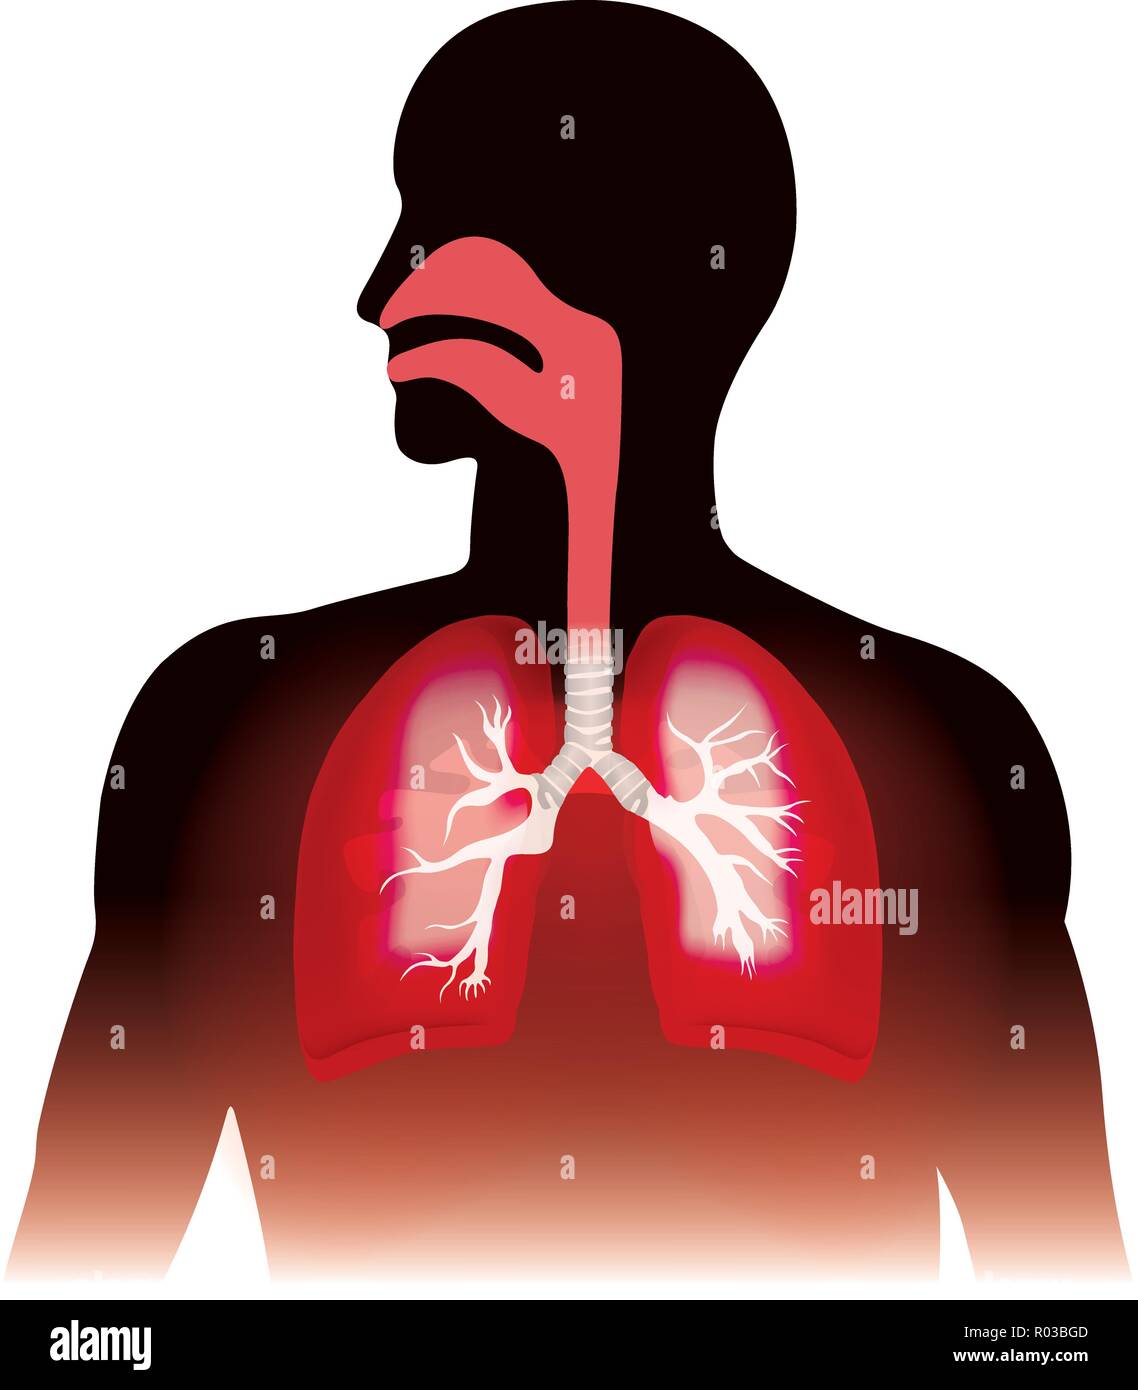

I polmoni e la respirazione umana. Anatomia grafica, illustrazione. Illustrazione Vettorialehttps://www.alamy.it/image-license-details/?v=1https://www.alamy.it/i-polmoni-e-la-respirazione-umana-anatomia-grafica-illustrazione-image223809725.html

I polmoni e la respirazione umana. Anatomia grafica, illustrazione. Illustrazione Vettorialehttps://www.alamy.it/image-license-details/?v=1https://www.alamy.it/i-polmoni-e-la-respirazione-umana-anatomia-grafica-illustrazione-image223809725.htmlRFR03BGD–I polmoni e la respirazione umana. Anatomia grafica, illustrazione.